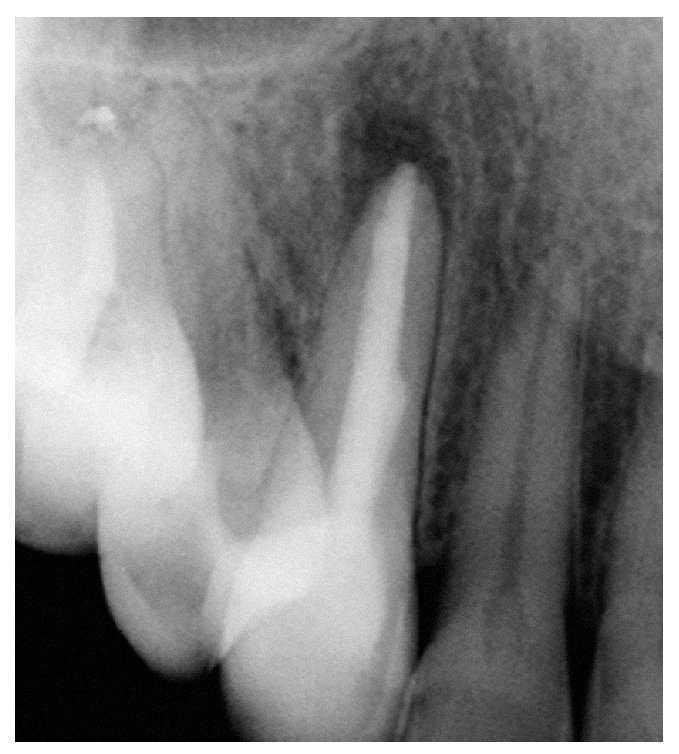

Figura 1a. Un cálculo pulpar obstruye la entrada del conducto radicular palatino del diente 16.

Figura 9a. Radiografía del diente 13 con perno metálico y periodontitis apical.

Figura 9b. La tomografía computarizada de haz cónico muestra la posición del perno en el conducto radicular desde mesial.